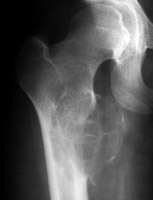

Aneurysmal bone cyst

Frontal radiograph of the right hip and CT scan of the hips on a different patient. Both reveal a cystic bubbly lesion with fine internal septations. Additionally, compromise of the cortical margin of the lesion is present as well. The "blister of bone" sign refers to a bubbly cystic lesion with a saccular protrusion of the cortex with multiple fine internal septae. The shell of the lesion may fracture resulting in extravasation of blood into the adjacent tissues. This sign is highly characteristic of aneurysmal bone cyst.

AP hip - Click on the image for a larger versionA - Click on the image for a larger versionB